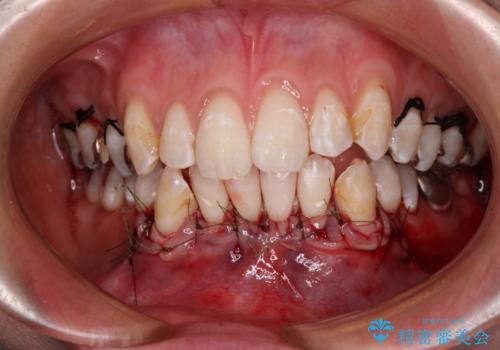

歯肉退縮に対して、上顎からの結合組織移植術(CTG)により、歯根の被覆を行うとともに、歯肉の厚みを増すことで将来の退縮リスクを抑制することとしました。

被覆量が不十分の場合には、追加で手術を行うことで患者様の了解を得ました。

上顎両側から歯肉を採取したたため、術後は痛みや出血で辛い思いをされましたが、1回の処置で満足のいく結果となりました。